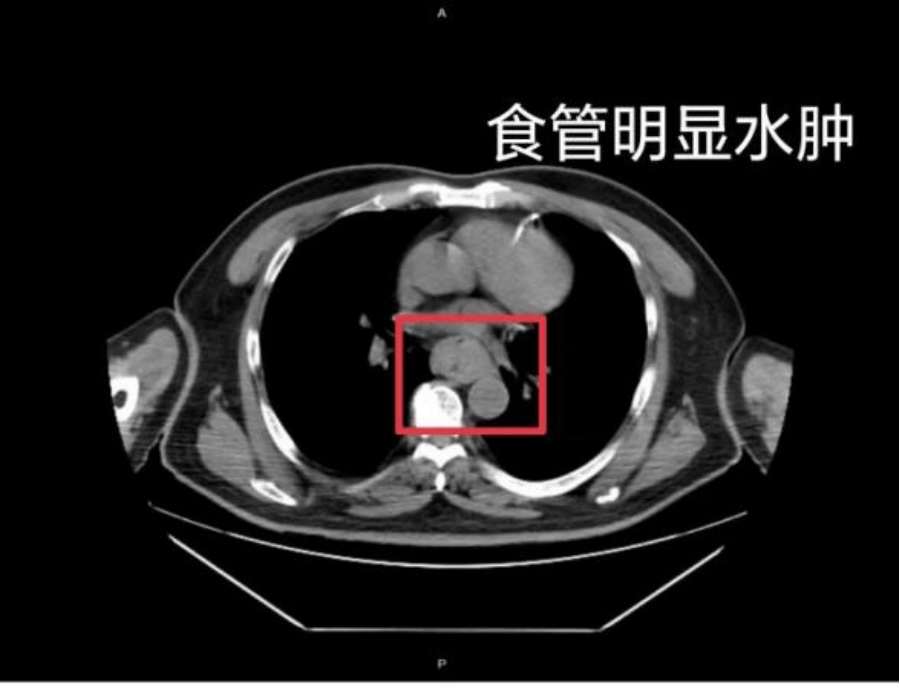

这样的情况并非个例,同样在近日,福州一位网友分享了自己因吃了一碗很烫的福鼎肉片导致呕血,并查出食管水肿的经历买卖虚拟币。

据网友回忆,“自己去厕所尝试呕吐时,直接呕出了血,一大口鲜血从嘴里喷出,总共吐了两次买卖虚拟币。”CT 结果显示,他的食管全部出现水肿损伤。